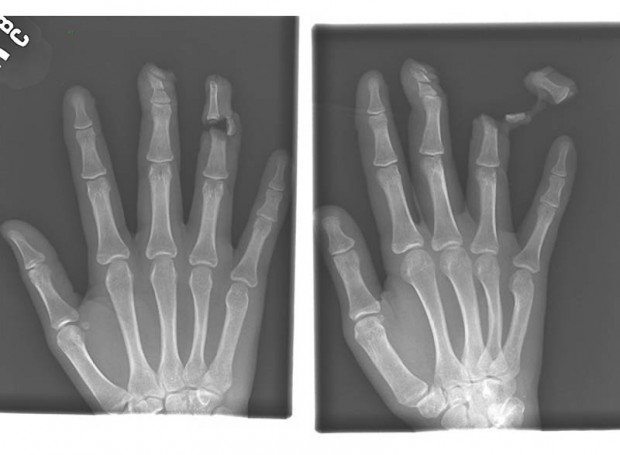

4. Гвоздь в костях указательного и среднего пальцев взрослого мужчины.